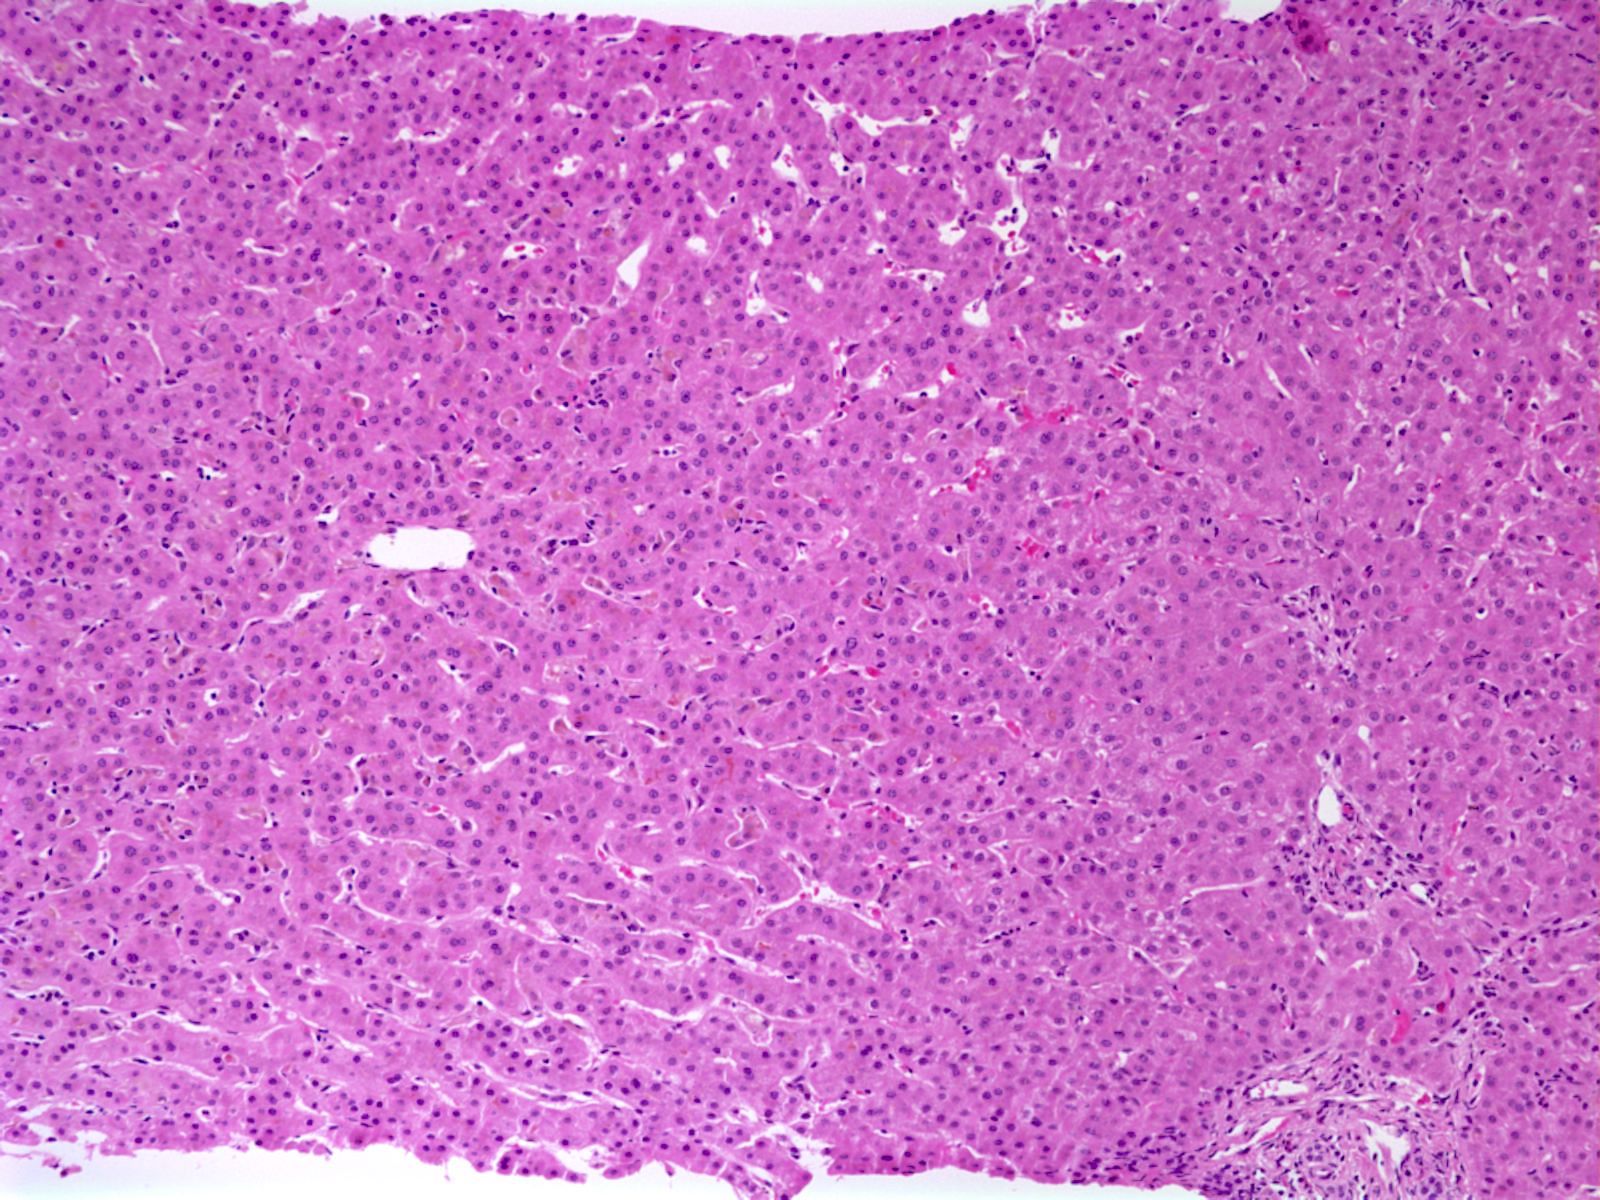

Microscopic (histologic) description

- Canalicular and intracellular cholestasis with associated hepatocyte rosettes

- No associated inflammation, bile duct loss or marked ductular reaction

- No advanced fibrosis

- Reference: Case Rep Gastrointest Med 2020;2020:2894293

Microscopic (histologic) images

Sample pathology report

- Liver, biopsy:

- Liver parenchyma with mild cholestasis (canalicular and intracellular); no fibrosis (see comment)

- Comment: The patient's history of recurrent attacks of jaundice and pruritis are noted. Sections show liver core biopsies with bland cholestasis (both canalicular and intracytoplasmic). No associated inflammation, bile ductular reaction or bile duct loss is seen. No fibrosis is seen.